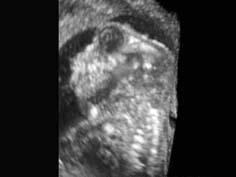

问题 26岁孕妇,既往体健,孕7周时常规产前B超检查未见异常,孕19周时检查,声像图如下图所示,根据图像所示,最有可能诊断的胎儿畸形是 ( )

选项 A、脊膜膨出 B、以上都不是 C、无脑儿 D、脑膨出 E、脊柱裂

答案 C